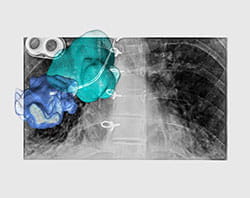

The room is equipped with all of the advanced radiology technology a surgeon may need. This includes X-ray, fluoroscopy (live X-ray), ultrasound and computed tomography (CT). Surgeons work side by side in the hybrid OR with interventional radiologists, who specialize in using these imaging technologies.

Imaging can be performed in the hybrid OR just before the surgery to help plan the procedure, during the surgery to identify important anatomy or disease, and after the surgery to evaluate results. In some situations, the surgeon will pull up images taken prior to surgery and overlay them with images taken in the hybrid OR. This can provide important details and help improve safety and accuracy.

In addition, the technology can help surgeons see their surgical tools as they navigate them inside the patient’s body. This improves surgical accuracy and helps surgeons avoid critical structures.